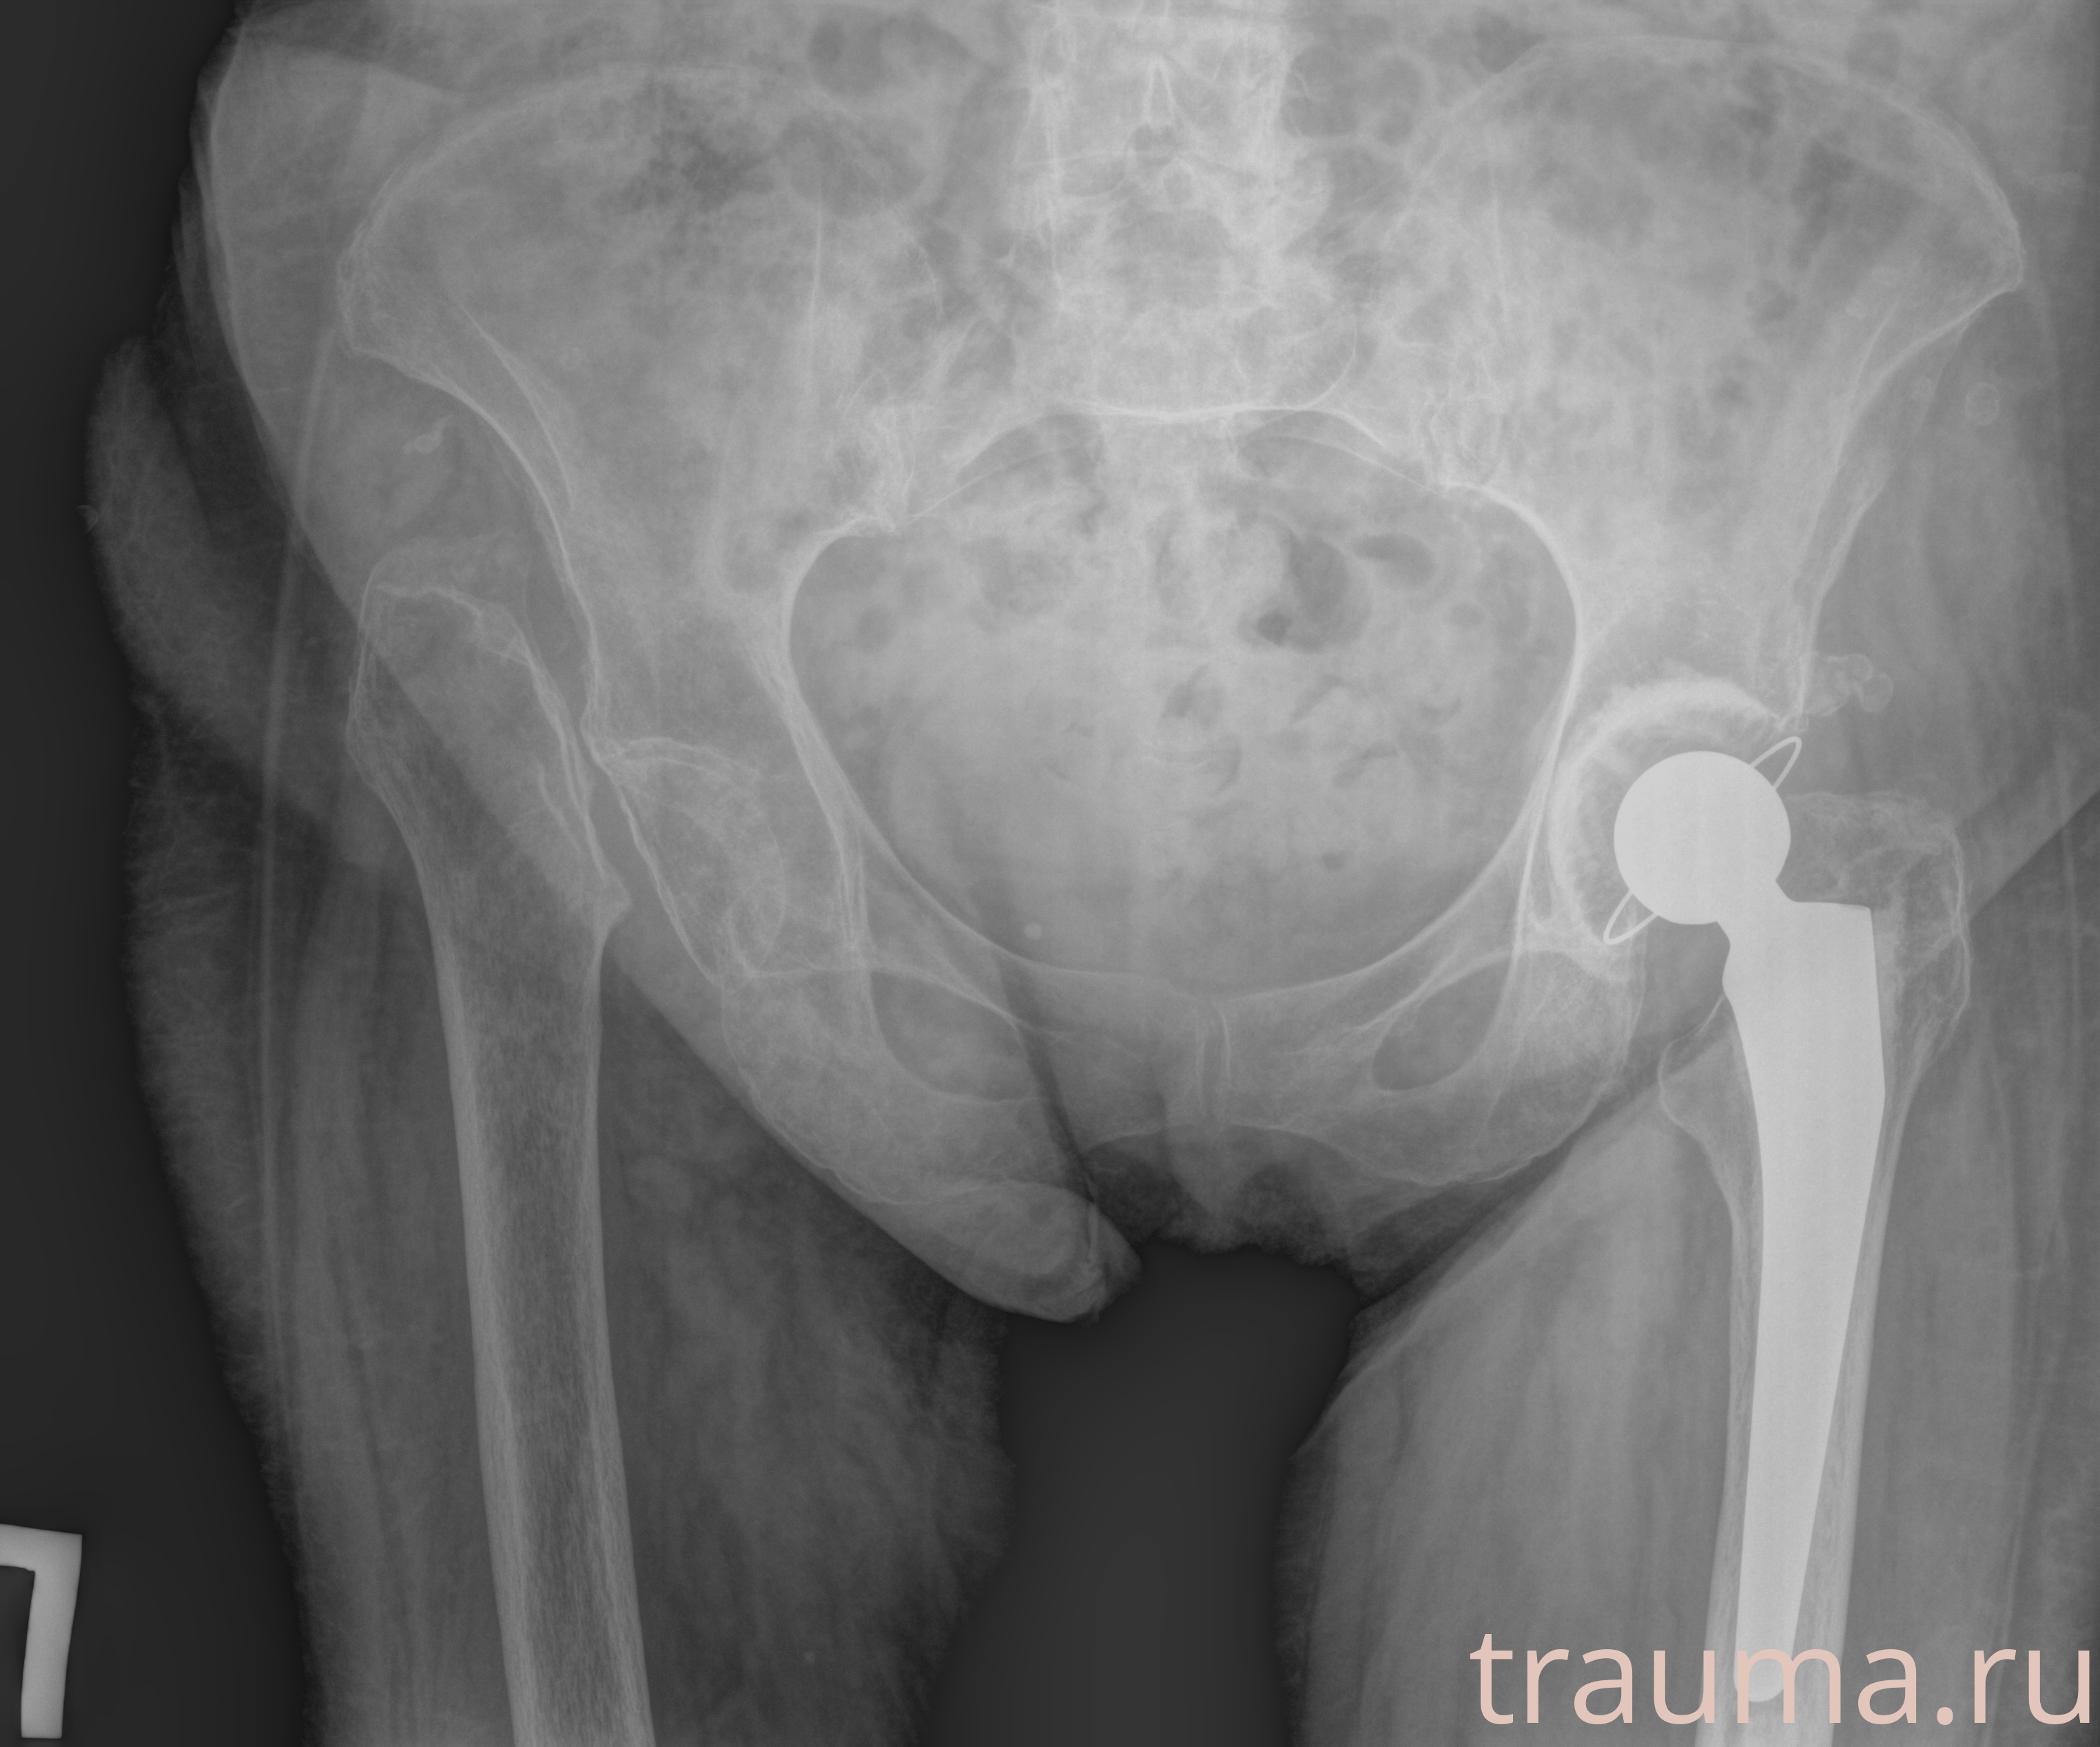

Рентгенограммы